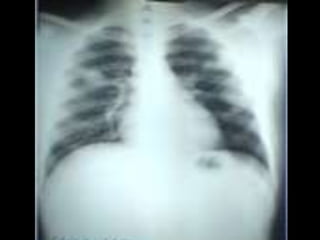

• C’est untéléthorax de face objectivant de multiples opacités de tonalité hydrique, de taille miliaire et micronodulaire diffuse, intéressant les 2 champs pulmonaires. • L’index cardio-thoracique est normal, les culs de sacs pleuraux sont libres et on note l’absence de lésions osseuses visibles .Conclusion : syndrome interstitiel diffus bilatéral évoquant une miliaire tuberculeuse en 1er lieu. Diagnostic différentiel : miliaire carcinomateuse, pneumoconiose (maladie professionnelle) • CAT : Echographie abdomino- pelvienne (car il existe des miliaires spléniques, hépatiques ou rénales. TDM thoracique, scintigraphie osseuse°